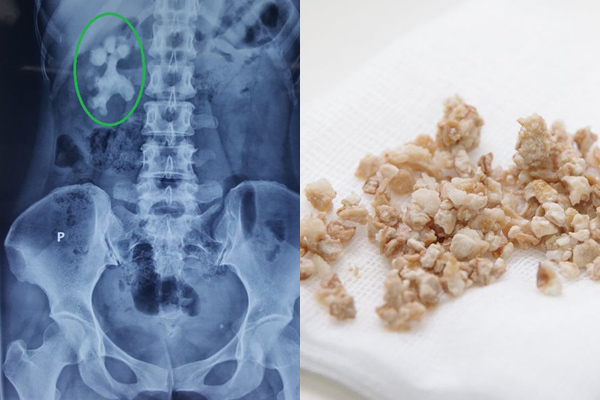

6 thói quen gây sỏi thận, cái thứ 3 người Việt mắc nhiều nhất, ai không có xin chúc mừng